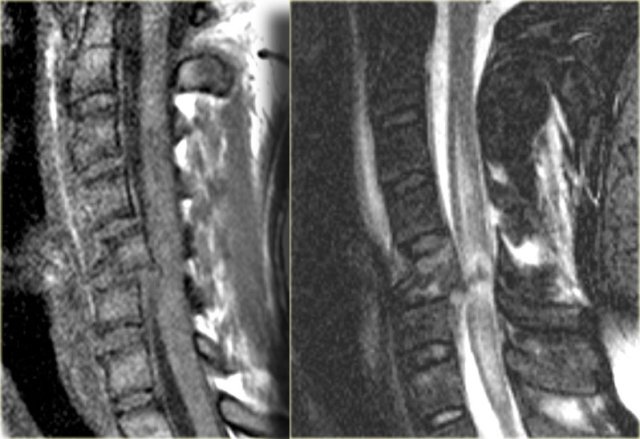

Flexion tear drop fracture (2)

Look for additional findings on the MR-images and then continue reading.

The findings are:

- Sof tissue injuries anteriorly and posteriorly with flavum and interspinous ligament rupture and CSF leakage.

- Hemorrhagic spinal cord injury!

Flexion tear drop fracture (3)

On the left images of a similar case.

There is a C5 flexion teardrop fracture.

Notice that the lower cervical area is not visualised well and additional imaging is required.

The CT-images demonstrate the extreme axial loading.

The tear drop fragment is displaced anteriorly and the larger part of the vertebral body is displaced posteriorly compressing the spinal cord.

Continue with the MR-images.

The MR-images demonstrate the spinal injury.

It is a hemorrhagic injury, which has a poor outcome.

Also notice the posterior ligamentous injury as a result of the hyperflexion with rupture of the ligamentum flavum and CSF leakage.

Notice the central location of the spinal cord injury.